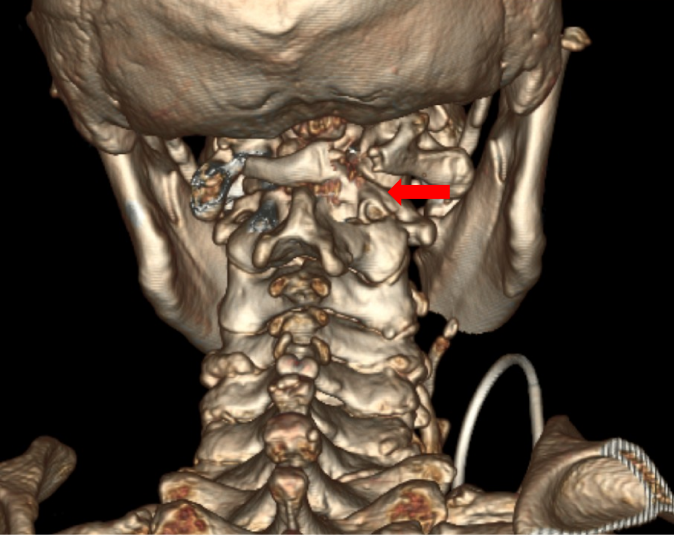

颈椎手术尤其是上颈椎手术的难度与风险很高,常被誉为刀尖上的舞蹈。术前的全面检查显示,该例患者与常见的上颈椎游离齿突畸形不同——引起颈髓损伤的主要原因不是寰枢椎不稳,而是齿突后方的异常骨性增生严重压迫脊髓所致。目前常用的手术解除脊髓压迫方法是经口咽途径直接切除游离的齿突及增生的骨性结构,再从后方行枕颈固定融合。但是这种手术不仅难度高而且有大量并发症风险,更是会令患者失去头部旋转功能的风险。最初姜主任团队一度考虑采用该常规手术方案,但对于这位72岁的高龄患者而言,创伤与风险是巨大的。

姜主任携团队成员将这个特殊病例资料同国内上颈椎领域的顶尖专家进行了详细的讨论,提出了一种新的手术方案:采用近年来兴起的单侧双通道(UBE Unilateral Biportal Endoscopy)脊柱内镜技术从颈椎后方进行微创手术。这是一种全新的尝试,相比常规术式难度更高,但具有不影响寰枢椎的稳定性的优势,是不需要经过枕颈融合操作的微创手术。若能达到有效的减压,即可改善神经症状并恢复脊髓功能。姜主任及团队不仅具备丰富的上颈椎手术经验,且在近年来已经开展了包括颈胸椎疑难病例在内的多例UBE脊柱微创手术,具有开展本例高难手术的技术保障。